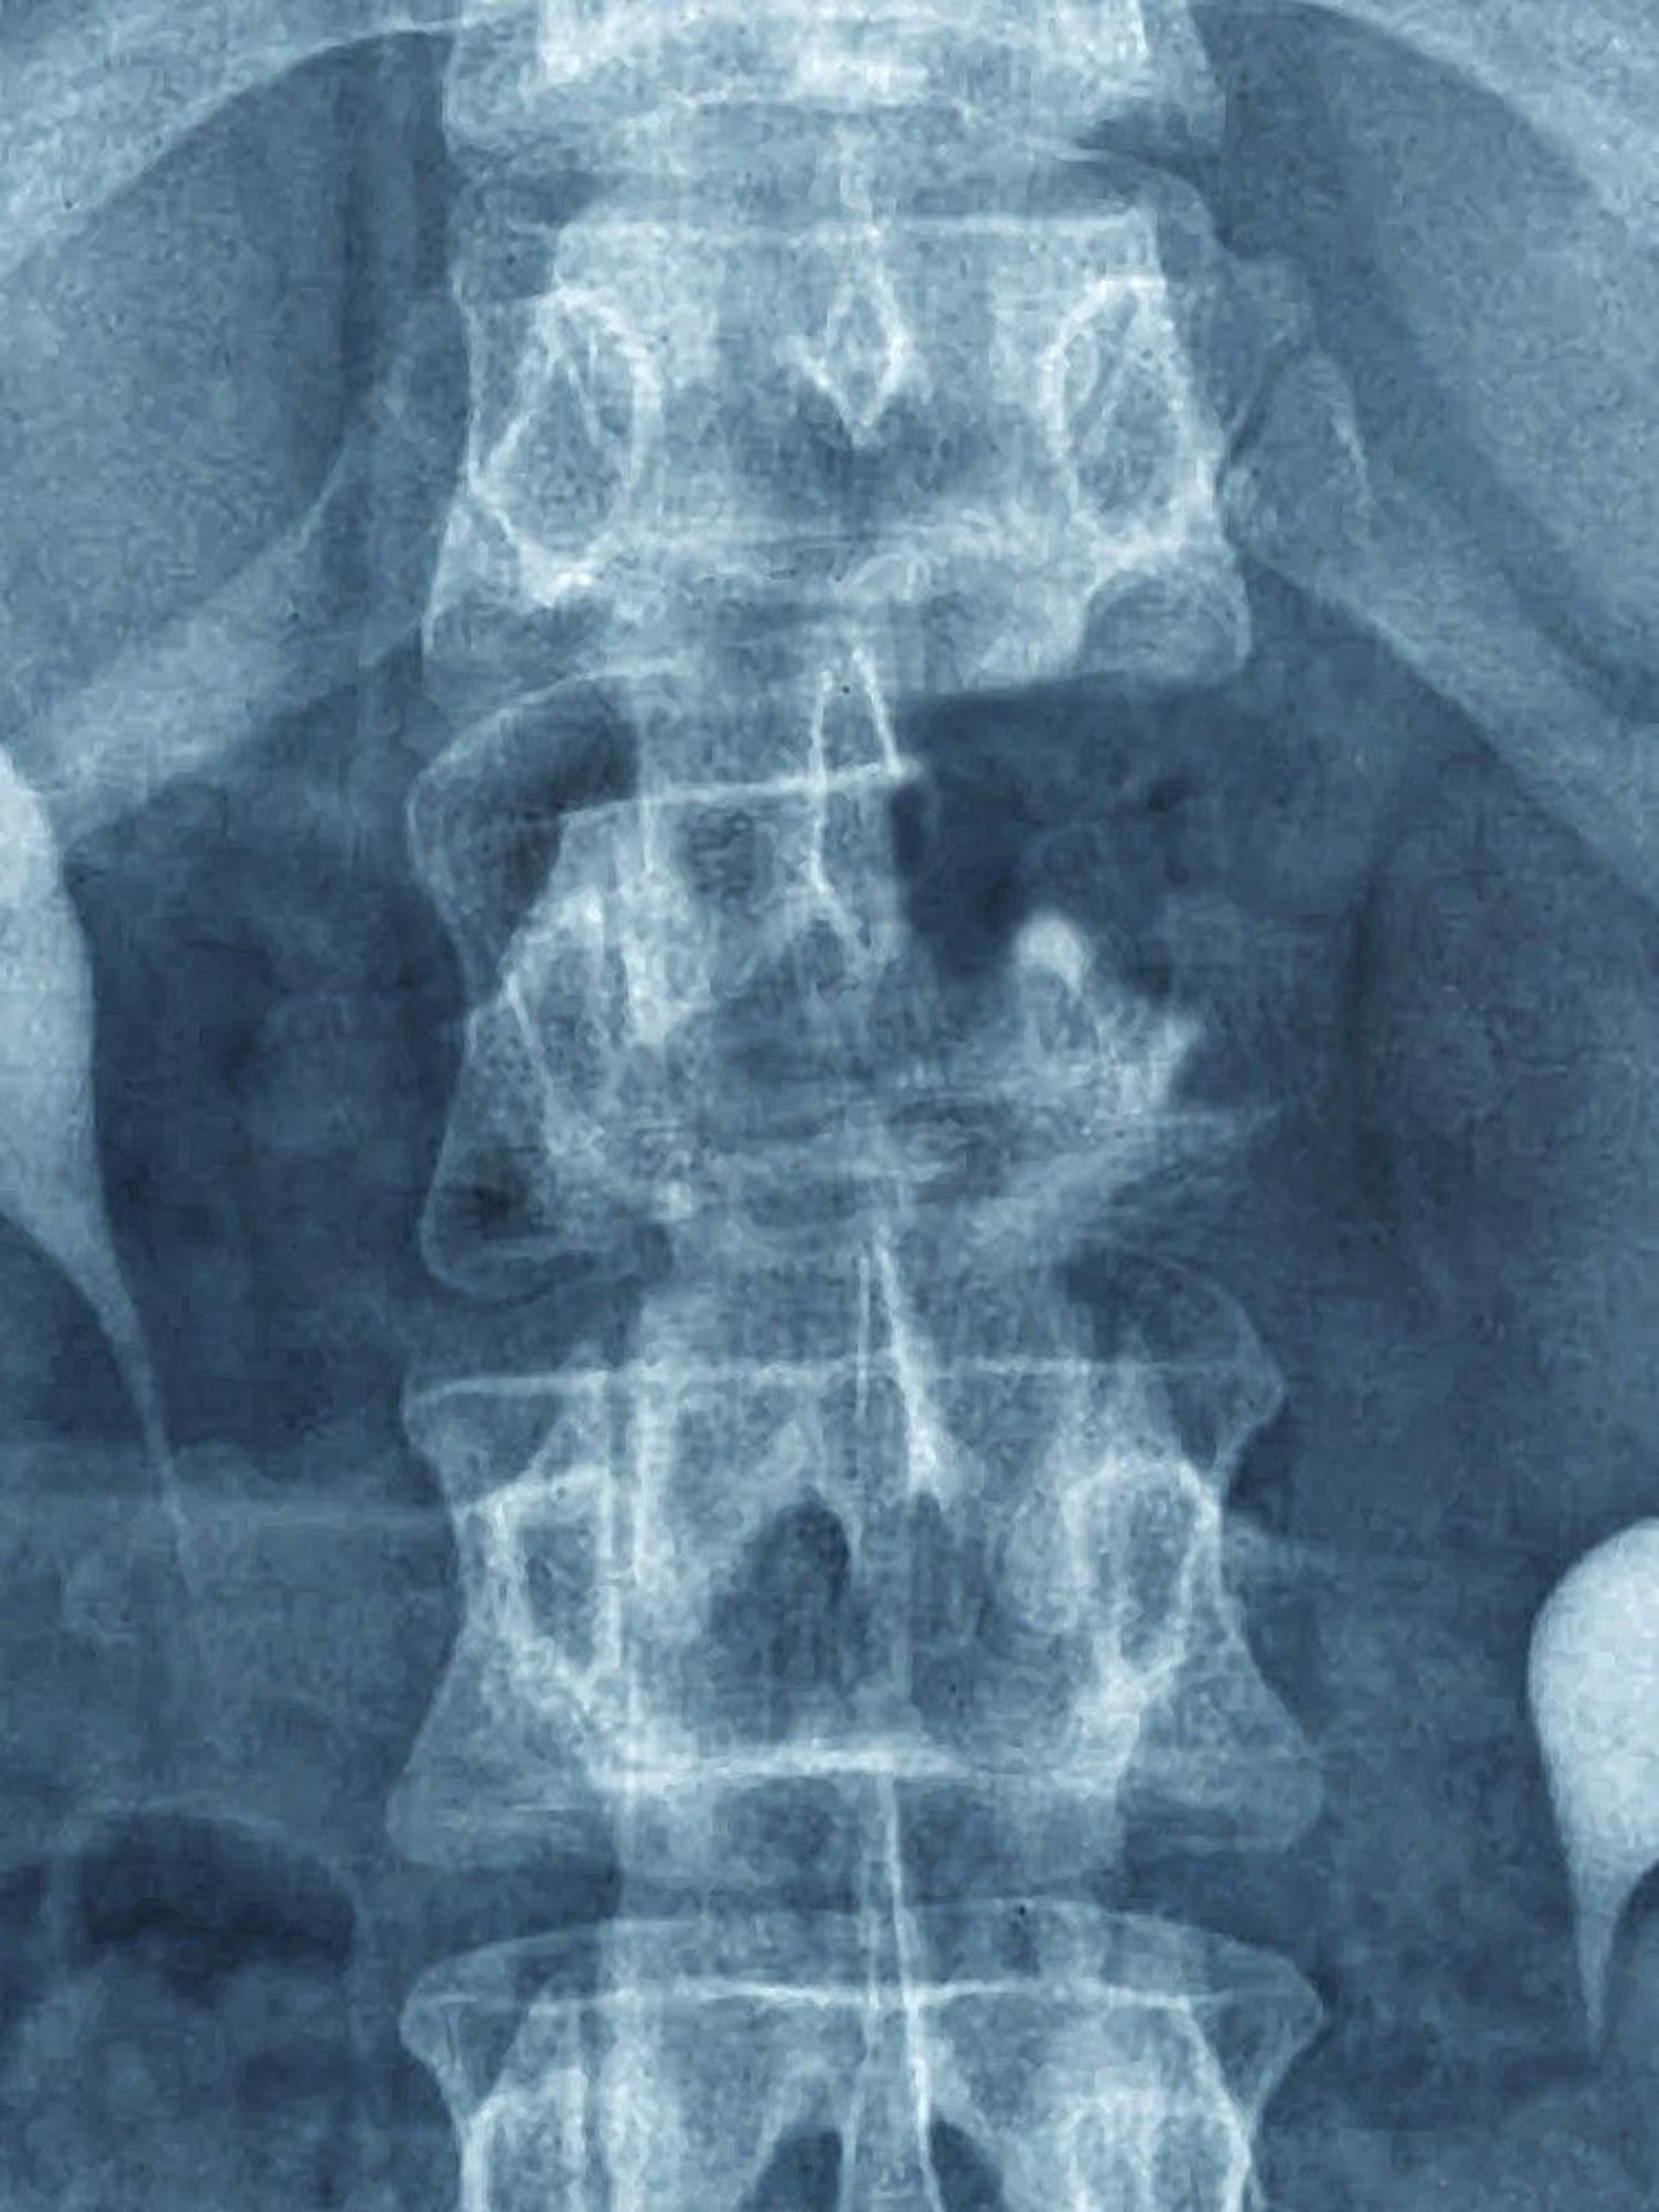

This metastasis is visible on plain radiographs as a destructive lesion affecting the upper part of the L1 vertebra (note the missing pedicle).

CAVALLINI JAMES/BSIP/SCIENCE PHOTO LIBRARY